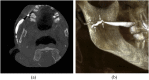

Methods: Patients with parotid or submandibular salivary symptoms were examined by 3D-CBCT sialography. They received an intraductal injection of 0.5 mL of water-soluble contrast medium maintained in the gland, followed by examination in a NewTom wide-field CBCT device. Images were processed with multiplanar and 3D reconstructions.

Results: A ductal exploration could be performed until the fourth divisions. The main lesions found were stones, stenosis, dilatations and "dead tree" appearance of the ductal system. No side effects of the catheterization or the iodine contrast were reported, nor tissue damages related to the contrast keeping technique.